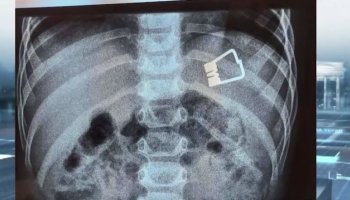

Σύμφωνα με πληροφορίες, η δημοτική σύμβουλος παρουσιαζόταν σαν ιατροδικαστής με σπουδές στο Αριστοτέλειο Πανεπιστήμιο και με το πρόσχημα της γνωριμίας με εξιδεικευμένους άλλους γιατρούς και κέντρα, υποσχόταν σε καρκινοπαθείς «ενδεδειγμένα» φάρμακα, φυσικά με το αζημίωτο. Τα θύματά της, πολλά κι όχι μόνο στη Θεσσαλονίκη, αλλά σε όλη τη βόρεια Ελλάδα.

Η κομπογιαννίτισα δεν δίσταζε μάλιστα να μπαίνει στα νοσοκομεία, όπως το ΑΧΕΠΑ, και να βγάζει φωτογραφίες φορώντας την ποδιά χαρτιού μαζί με τους ασθενείς. Η δράση της εκτείνεται σε ολόκληρη τη βόρεια Ελλάδα, με θύματά της μέχρι και επαγγελματίες οδηγούς που ήθελαν να εξασφαλίσουν άδεια επαγγέλματος.